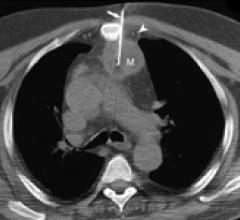

August 23, 2010 - Two companies recently signed a strategic partnership agreement drawing on both firms' established expertise in imaging technology to establish computed tomography (CT) as a viable, minimally-invasive imaging alternative for many cardiovascular procedures.

August 18, 2010 - Cardiac computed tomography (CT) was found to be safe, accurate, and cost-effective in low risk patients in a recent scientific statement published by the American Heart Association (AHA), titled “Testing of Low-Risk Patients Presenting to the Emergency Department With Chest Pain.”

August 18, 2010 - Researchers from Mount Sinai School of Medicine have for the first time developed a way to visualize coronary artery plaques vulnerable to rupture using multicolor computed tomography (CT), an innovation that may lead to better and earlier diagnosis of cardiovascular disease. The data are published in the September issue of Radiology.